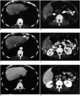

Necrotic liver tumor